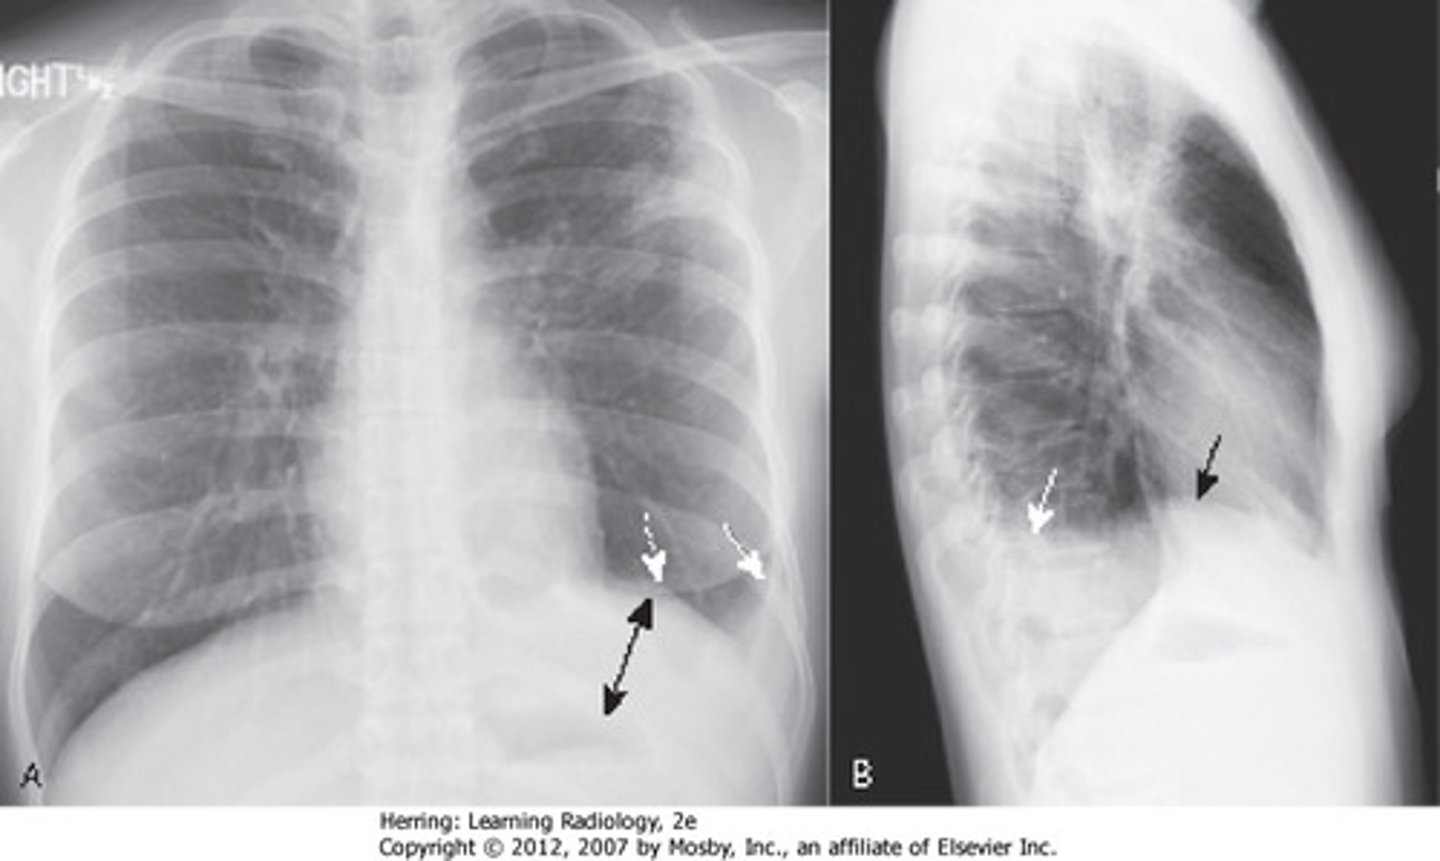

pleural cavities

knowt flashcard image